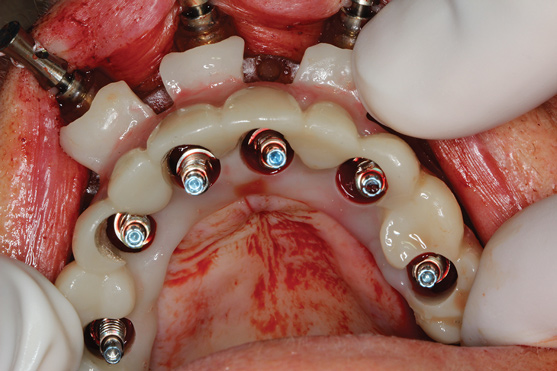

The workflow described in this case is just one example, and there are numerous ways to achieve the same goal. This particular workflow is relatively easy to execute and efficient from the standpoint of planning, fabrication, and clinical application. Figure 11 and Figure 12 demonstrate the accurate placement of the implants as can be seen by the copings exiting directly into the openings in the printed provisional. The provisional was indexed and the copings picked-up by injecting a provisional bisacryl composite resin. The finished 3D-printed provisional was characterized with pink composite and fixated to the implants with abutment screws, and the access holes were sealed with sterilized teflon tape and composite resin (Figure 13).

Fig 13. Retracted view after immediate delivery of characterized provisional prosthesis.

Figure 13